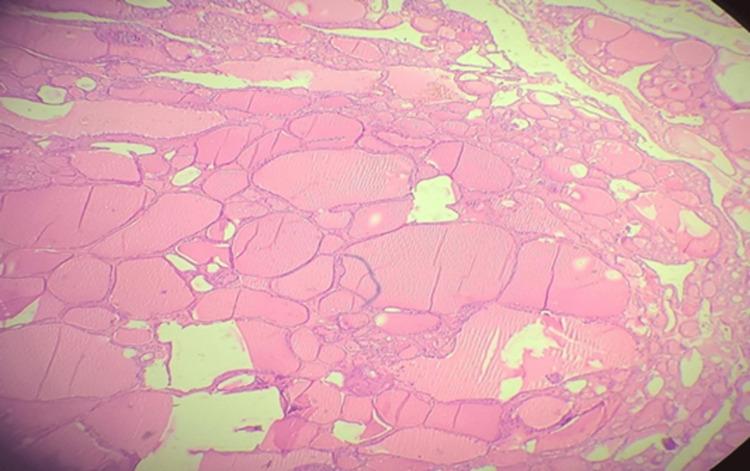

Ectopic thyroid is a rare clinical presentation to encounter in day-to-day clinical practice. It occurs due to developmental defects in the early stages of the thyroid gland embryogenesis during its descent from the floor of the primitive foregut to its final pre-tracheal position. It is usually present along the extent of the thyroglossal duct as well as in distant locations such as sub-diaphragmatic or mediastinal spaces. The diverse clinical presentation of this rare entity often causes a diagnostic dilemma. A thyroid scintigraphy scan is pivotal in the diagnosis of ectopy, but ultrasonography is done more frequently. Surgical management is preferred for symptomatic cases, followed by radioactive iodine ablation and levothyroxine supportive therapy for refractory cases. We present a case of a 62-year-old female patient who presented with pain and swelling of the right submandibular region. On ultrasonography, a 5*4 cm firm mobile swelling of the right submandibular region was found, suggestive of right submandibular sialadenitis. Fine needle aspiration cytology (FNAC) was subsequently done, and it showed features of basaloid neoplasm like pleomorphic adenoma, and as the thyroid tissue was in an ectopic location, it must have been misdiagnosed. The patient was then taken up for right submandibular sialoadenectomy, and the histopathological examination of the operative specimen showed nodular colloidal goiter and mild chronic sialadenitis. Ectopic thyroid can present at various anatomical locations and thereby has varied clinical presentations which makes it a diagnostic dilemma for clinicians. The usual radiological investigations done include USG and CT scan, whereas thyroid scintigraphy is more precise in reaching the diagnosis of ectopic thyroid. The confirmatory diagnostic method is the histopathological examination of the excised specimen. Most cases of ectopic thyroid are asymptomatic and require regular follow-up. Symptomatic cases are managed by surgical excision followed by periodic monitoring and adequate thyroxine replacement.

异位甲状腺是日常临床实践中少见的临床表现。它是由于甲状腺在胚胎发育早期从原始前肠底部下降至气管前最终位置的过程中出现发育缺陷所致。它通常出现在甲状舌管走行的范围内,也可出现在如膈下或纵隔等较远的部位。这种罕见疾病多样的临床表现常导致诊断困难。甲状腺闪烁扫描在异位甲状腺的诊断中起关键作用,但超声检查更为常用。有症状的病例首选手术治疗,难治性病例则采用放射性碘消融及左甲状腺素支持治疗。我们报告一例62岁女性患者,她因右下颌下区疼痛和肿胀前来就诊。超声检查发现右下颌下区有一个5×4cm质地硬、可活动的肿物,提示右下颌下涎腺炎。随后进行了细针穿刺细胞学检查(FNAC),结果显示为基底样肿瘤特征,如多形性腺瘤,由于甲状腺组织位于异位位置,之前肯定被误诊了。该患者随后接受了右下颌下涎腺切除术,手术标本的组织病理学检查显示为结节性胶样甲状腺肿和轻度慢性涎腺炎。异位甲状腺可出现在不同的解剖位置,因此有多种临床表现,这给临床医生带来了诊断难题。通常进行的影像学检查包括超声检查(USG)和CT扫描,而甲状腺闪烁扫描在诊断异位甲状腺方面更为精确。确诊的诊断方法是对切除标本进行组织病理学检查。大多数异位甲状腺病例无症状,需要定期随访。有症状的病例通过手术切除治疗,随后进行定期监测和适当的甲状腺素替代治疗。